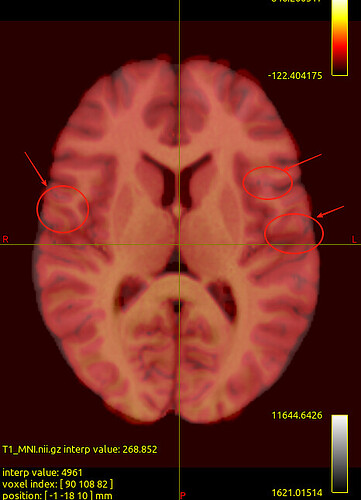

We noticed that the tck files already warped to MNI space are misaligned with the standard template in some sulcal and gyral regions. However, we also checked the registration between the T1 image and MNI space — even the T1 image warped to MNI space fails to align with the sulci and gyri of the MNI template. Nevertheless, the tck files in standard space show better alignment with the T1 image in MNI space. Can this be considered a good warping result? Figures are as follows.